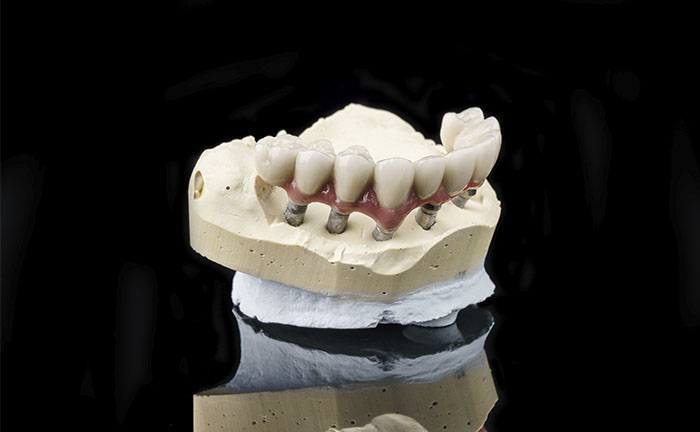

12 resin crowns (fixed teeth)

Another great advantage that derives from the All on 6 method is the immediate load, on the inserted implants your new fixed teeth are fixed in the same session or at most in a second sitting after a few days.

Performed treatments